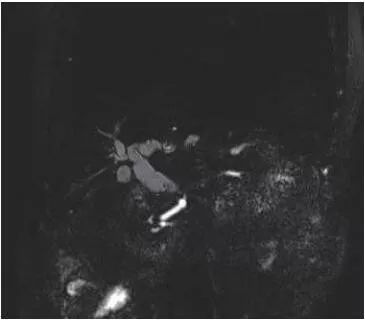

上腹部磁共振成像(MRI)检查结果显示,壶腹部异常信号结节,肝内外胆管、主胰管扩张,考虑肿瘤可能性大(图1)。十二指肠镜检查结果显示,主乳头呈菜花状肿块,病灶中央凹陷,外观充血、水肿,大小约3.0 cm×2.0 cm×2.0 cm(图2)。

图1 上腹部MRI示胆总管下端梗阻,胰管轻度扩张